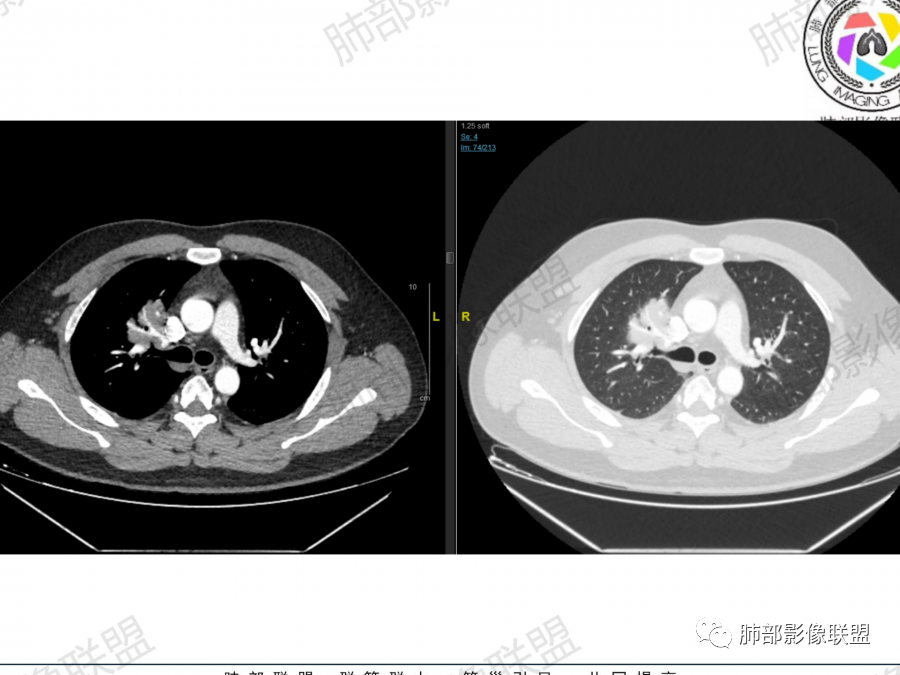

晨读:右肺多发实变影,较大位于肺尖,可见空洞,空洞形态不规则,洞壁较厚,部分可见支气管与空洞壁相连,右肺下叶可见多发结节影,平行胸膜,垂直血管束,部分与胸膜相连,边界清楚,纵隔淋巴结肿大。临床:咳嗽、气喘一个月,考虑结核,GPA,淋巴瘤

中年男性,病史不支持急性感染,影像,双肺多发结节肿块,右肺为主,肿块边缘膨隆,分叶,无明显毛刺及清晰磨玻璃影,病灶周围无树芽,肺气肿,肿块内支气管轻度扩张,血管走形自然,右肺上叶不是空洞,中间考虑正常肺组织,肿块包围?考虑,淋巴瘤,鉴别血管炎

右肺多发结节性病变,谷小空洞及多发结节融合改变,增强轻度的强化,有血管穿行,血管征。考虑肉芽肿性病变,结核或隐球菌感染。鉴别淋巴瘤。

右肺多发支气管血管,胸膜下结节,血管穿行自然,均匀强化。纵隔无明显肿大淋巴结,考虑原发性淋巴瘤,鉴别隐球菌。

晨读:青年男性。咳嗽气喘1月,胸部ct:右肺多发结节、肿块,沿着支气管血管束及胸膜下分布,边缘平直,清楚,内支气管基本通畅、轻微扩张,血管走形自然。考虑淋巴增殖性病变,淋巴瘤?注意鉴别血管炎、隐球菌病。

晨读,青年男性,咳嗽气喘病史,铁蛋白及D2聚体升高,右肺多发病灶,上叶团块影,深分叶,不均匀强化,可见血管征,支气管充气征,走形自然。右肺下叶背段球形阴影,有融合趋势,可见空洞,洞壁光滑,有血管自然通过,下叶外侧段靠近胸膜球形阴影,有血管进入,总体恶性证据多,淋巴瘤首选。

主要征象:右肺多发病变  一元论?二元论?

1.右上肺团块:分叶,不均性强化,其内支气管走行自然,增强血管影可见、清晰。

疑问:空洞还是残余肺组织?

2.右下肺结节、实变:胸膜下,长轴平行胸膜。部分似有晕影。支气管进入后近段截断